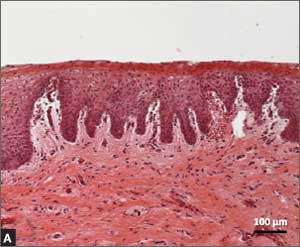

Recently published histology data highlight significant changes 1 month after fractional CO2 laser treatment that included a much thicker epithelium with wide columns of large epithelial cells rich in glycogen.21 Also noted was a significant reorganization of connective tissue, both in the lamina propria and the core of the papillae (FIGURES 1 and 2).

FIGURE 2: Atrophic vaginitis

This histologic preparation of vaginal mucosa sections shows untreated atrophic vaginitis (A) and the same mucosa 1 month after treatment with fractional CO2 laser therapy (B). Reprinted with permission from DEKA M.E.L.A. Srl (Calenzano, Italy) and Professor A. Calligaro, University of Pavia, Italy.